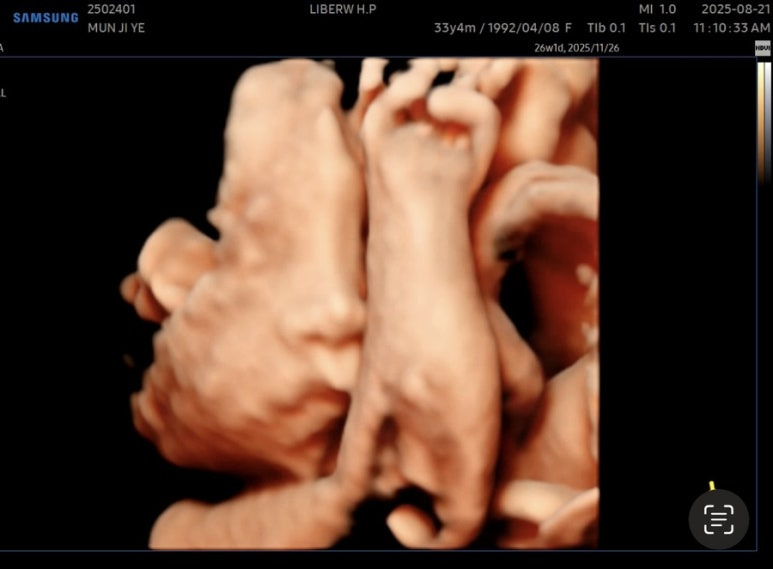

오랜만에 본 사탕이는

머리가 밑으로 잘 이동해있었다😊

잘 체크하고 드디어 얼굴을 보는 시간!!

아쉽게도

사탕이는 얼굴을 가리고 있었다🥲

안쪽에 팔로 얼굴 가리고 숨은 사탕

이 상태로 찍어봤지만,,,!

여기까지가 최선이었다^^,,,

또르르🥲

사탕아~~ 코만 구경하라는 거니~~~?

잘 안 보여서 다시 찍어볼 겸

사탕이가 왼쪽으로 누우면 잘 움직이길래

옆으로 누운 상태로

선생님이 열심히 흔들어주셨다!

하지만 결과는 그대로 ㅎㅎ

얼굴은 숨어버리고

손이랑 발만 보여줌 ㅎㅎㅎㅎㅎ

그것도 웅크리고 숨어있어서

손이랑 발도 제대로 못 찍고,,,